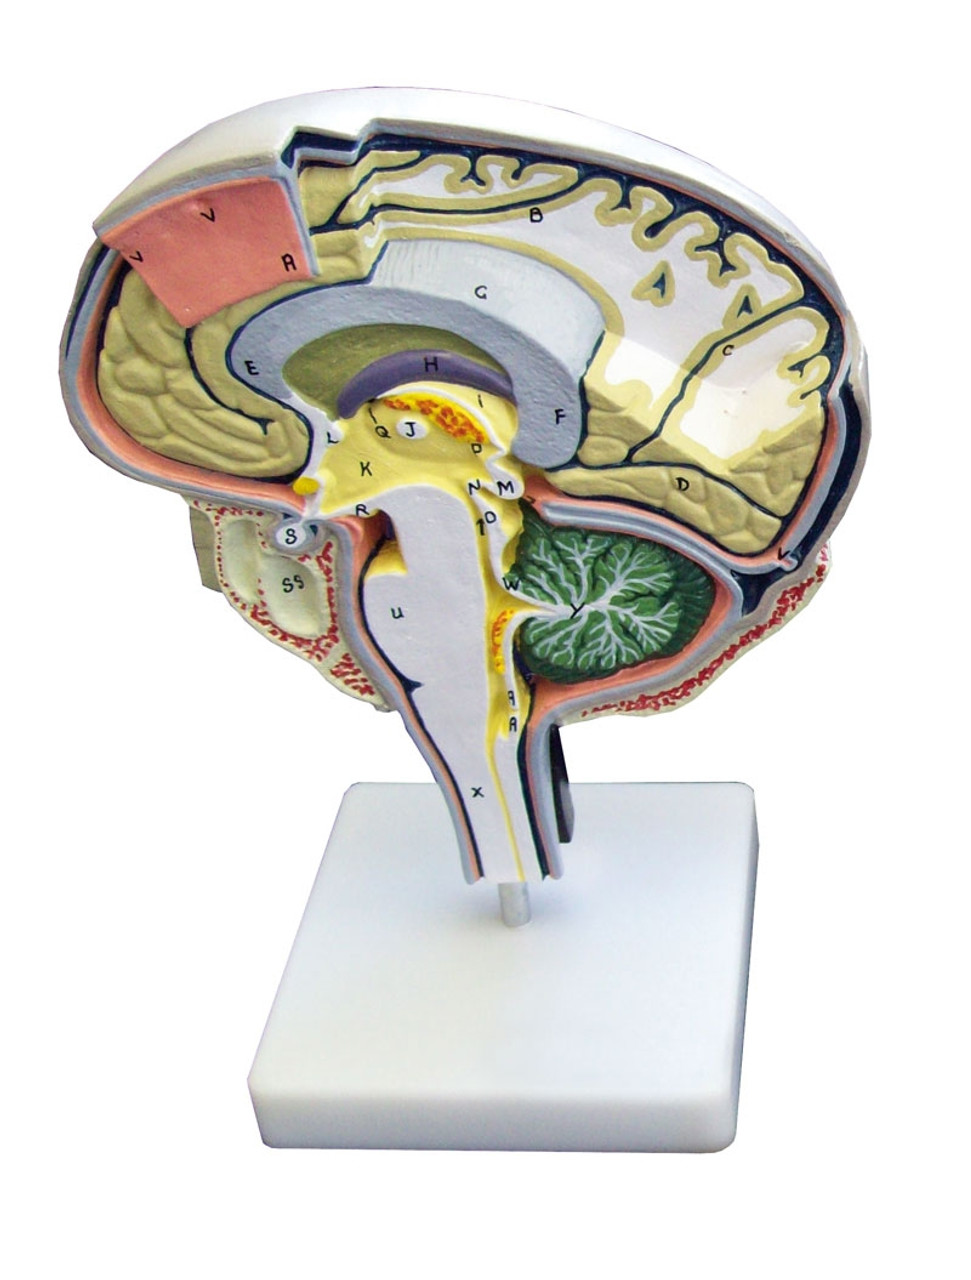

Сагиттальный разрез головного мозга (модель)